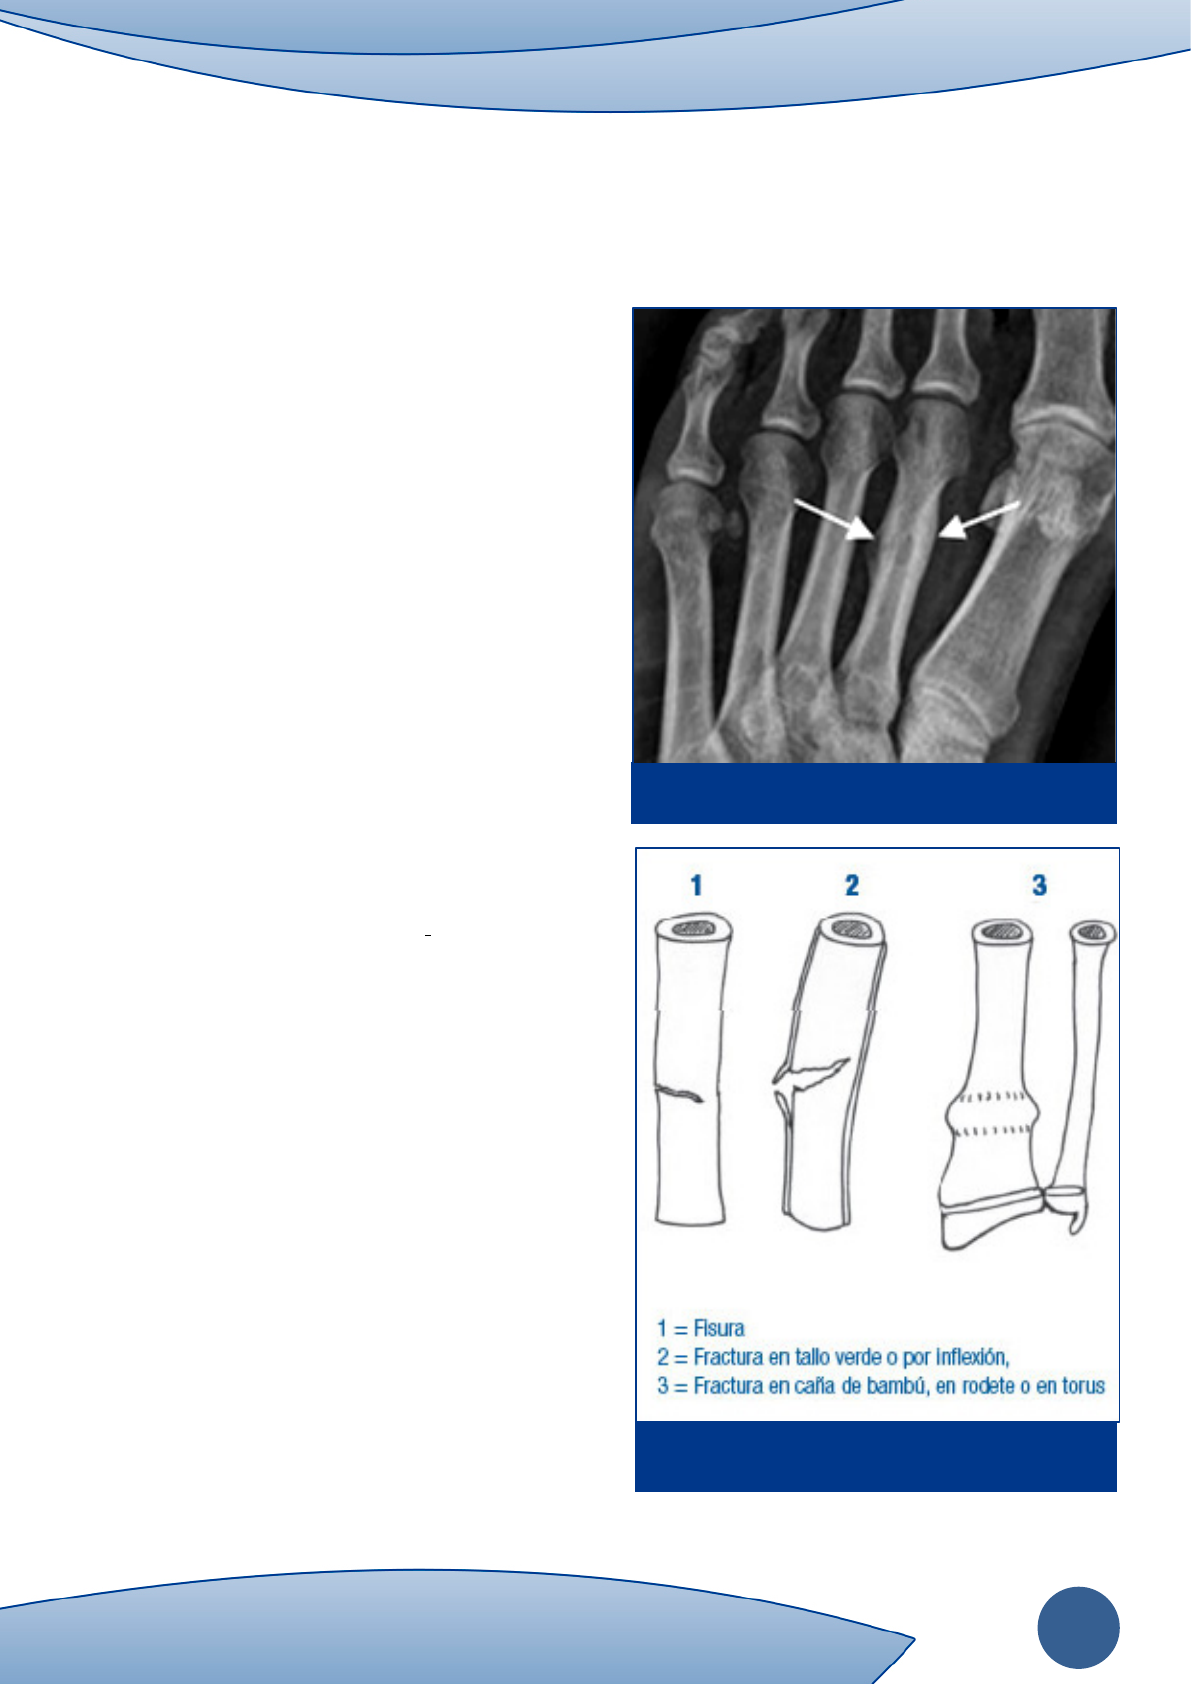

fractura de Deütschlander (Figura1).

• Fractura incompleta: Es aquella en la que el trazo no

afecta a todo el espesor del hueso (Figura 2).

a) Fisuras: afecta a parte del espesor.

b) Fracturas en tallo verde: típica en los niños,

suceden por flexión en huesos flexibles. Hay

solución de continuidad en la superficie de

tensión pero no progresa en la de compresión.

c) Fracturas en rodete: típica de los niños en las

zonas de unión metafiso-diafisarias. El hueso

cortical metafisario es insuflado por compresión

del eje vertical (2).

Figura 1.

Figura 2. Fisuras incompletas.